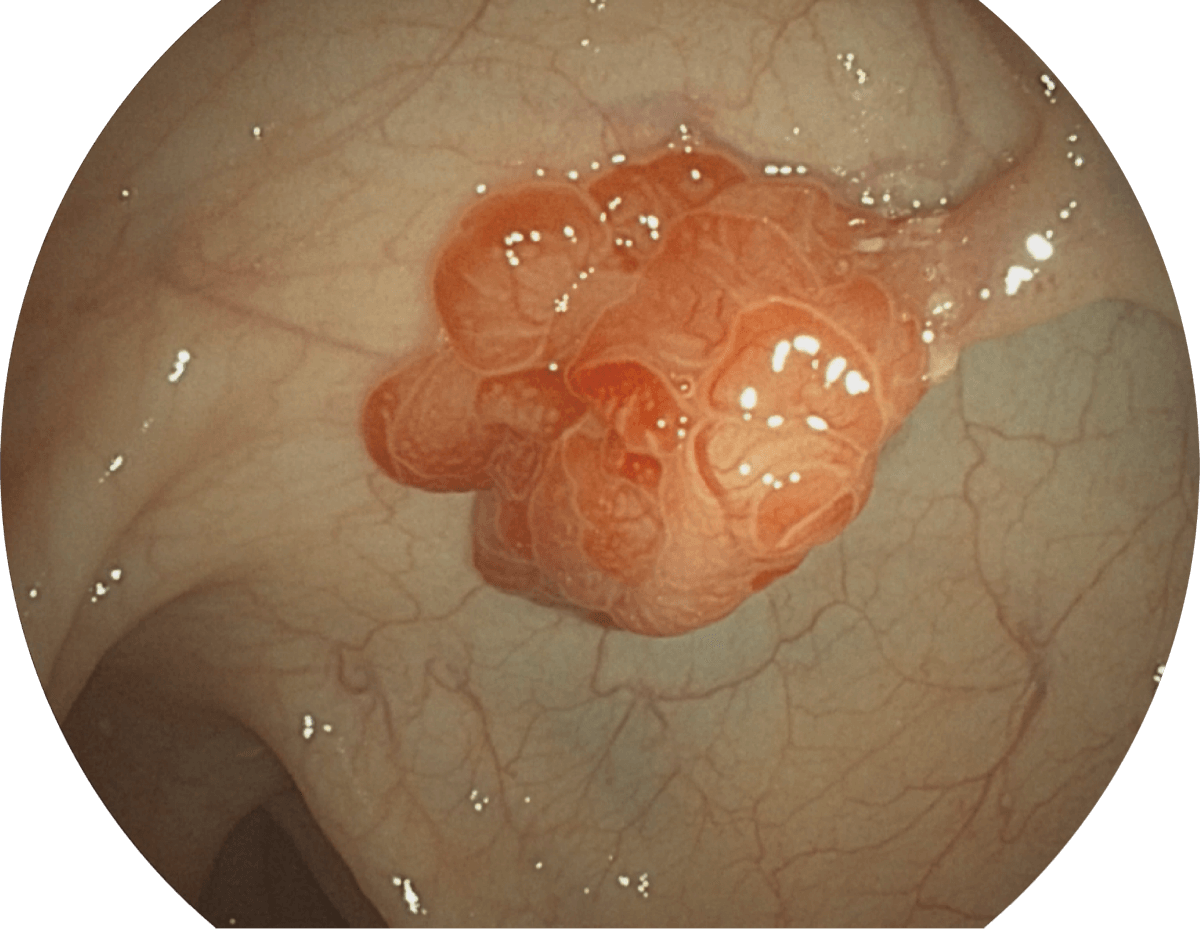

图像具有高亮度、高黏膜血管颜色对比度的特点,且不改变粘液、食物残渣、粪便的基本颜色,可在中远景下进行观察,助力消化道早期疾病的诊断。

• WL

• SFI

• VIST